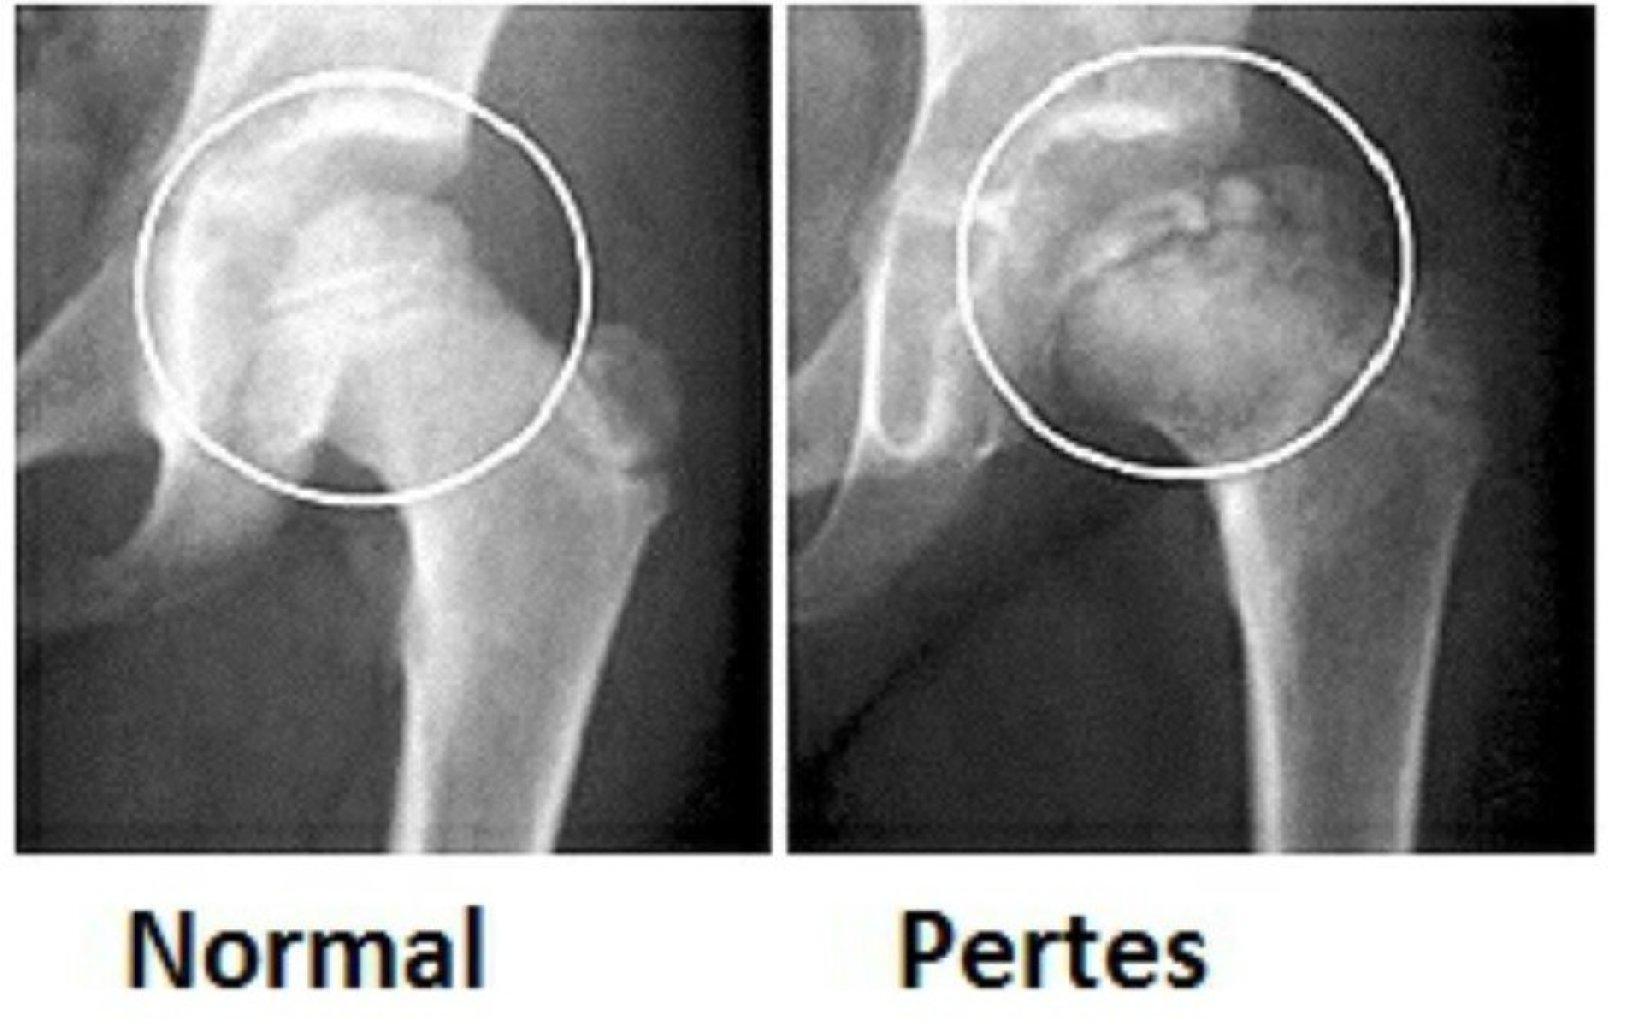

Perthes Xəstəliyində Risk Faktorları Perthes xəstəliyi bud sümüyünün yuxarı hissəsində bud sümüyü...